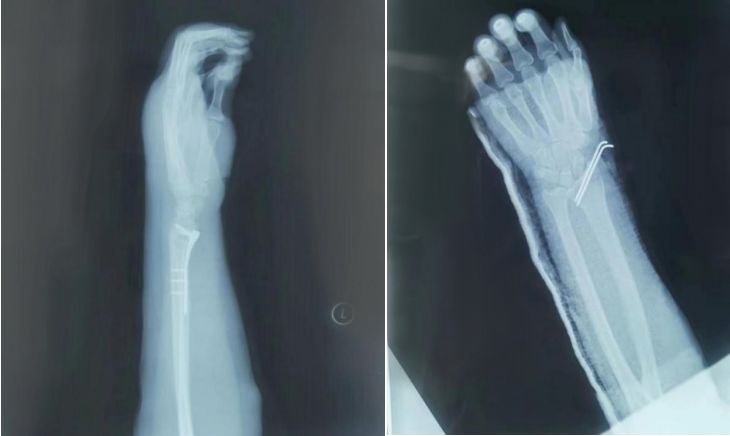

骨折复位前影像

AED怎么自检手腕摔伤后自检方法及诊疗释疑_https://www.jmylbn.com_新闻资讯_第6张

骨折复位后影像